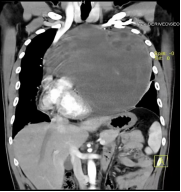

该患者去年8月突发胸闷于当地医院就诊,胸部CT发现了前纵隔巨大占位,大小约15.3cm×14.2cm。患者于当地医院进行穿刺确诊为“生殖细胞瘤”后进行3周期化疗,但是化疗后复查CT发现肿瘤进行性长大,今年2月前复查CT提示纵隔肿瘤最大截面“20.4cm×16.1cm”。患者心脏及纵隔大血管受压明显,本来位于左侧的心脏,被肿瘤挤压到了右侧胸腔,且出现了严重的呼吸系统和循环系统受累。跑遍各地多次求医无果后,患者及家属抱着最后一线希望找到我院肺癌中心周清华教授。

图1:患者术前胸部增强CT显示前纵隔巨大肿瘤